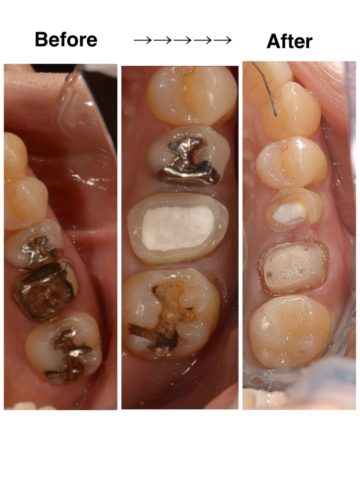

虫歯治療